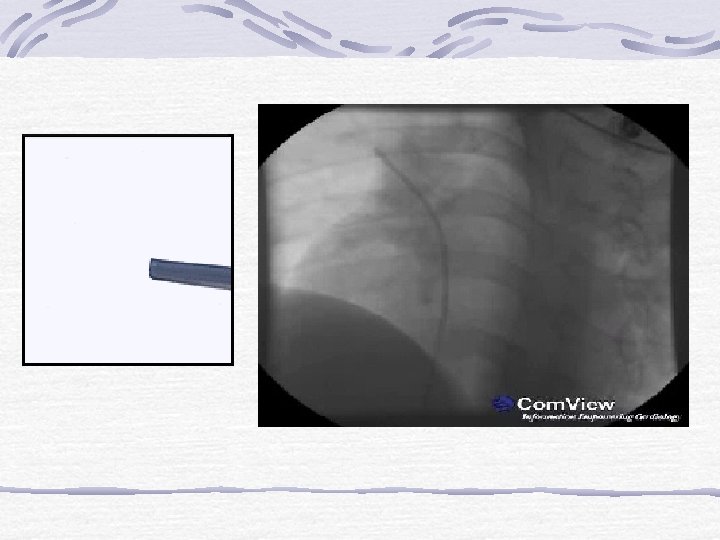

Kontrollü salınan “coiller”